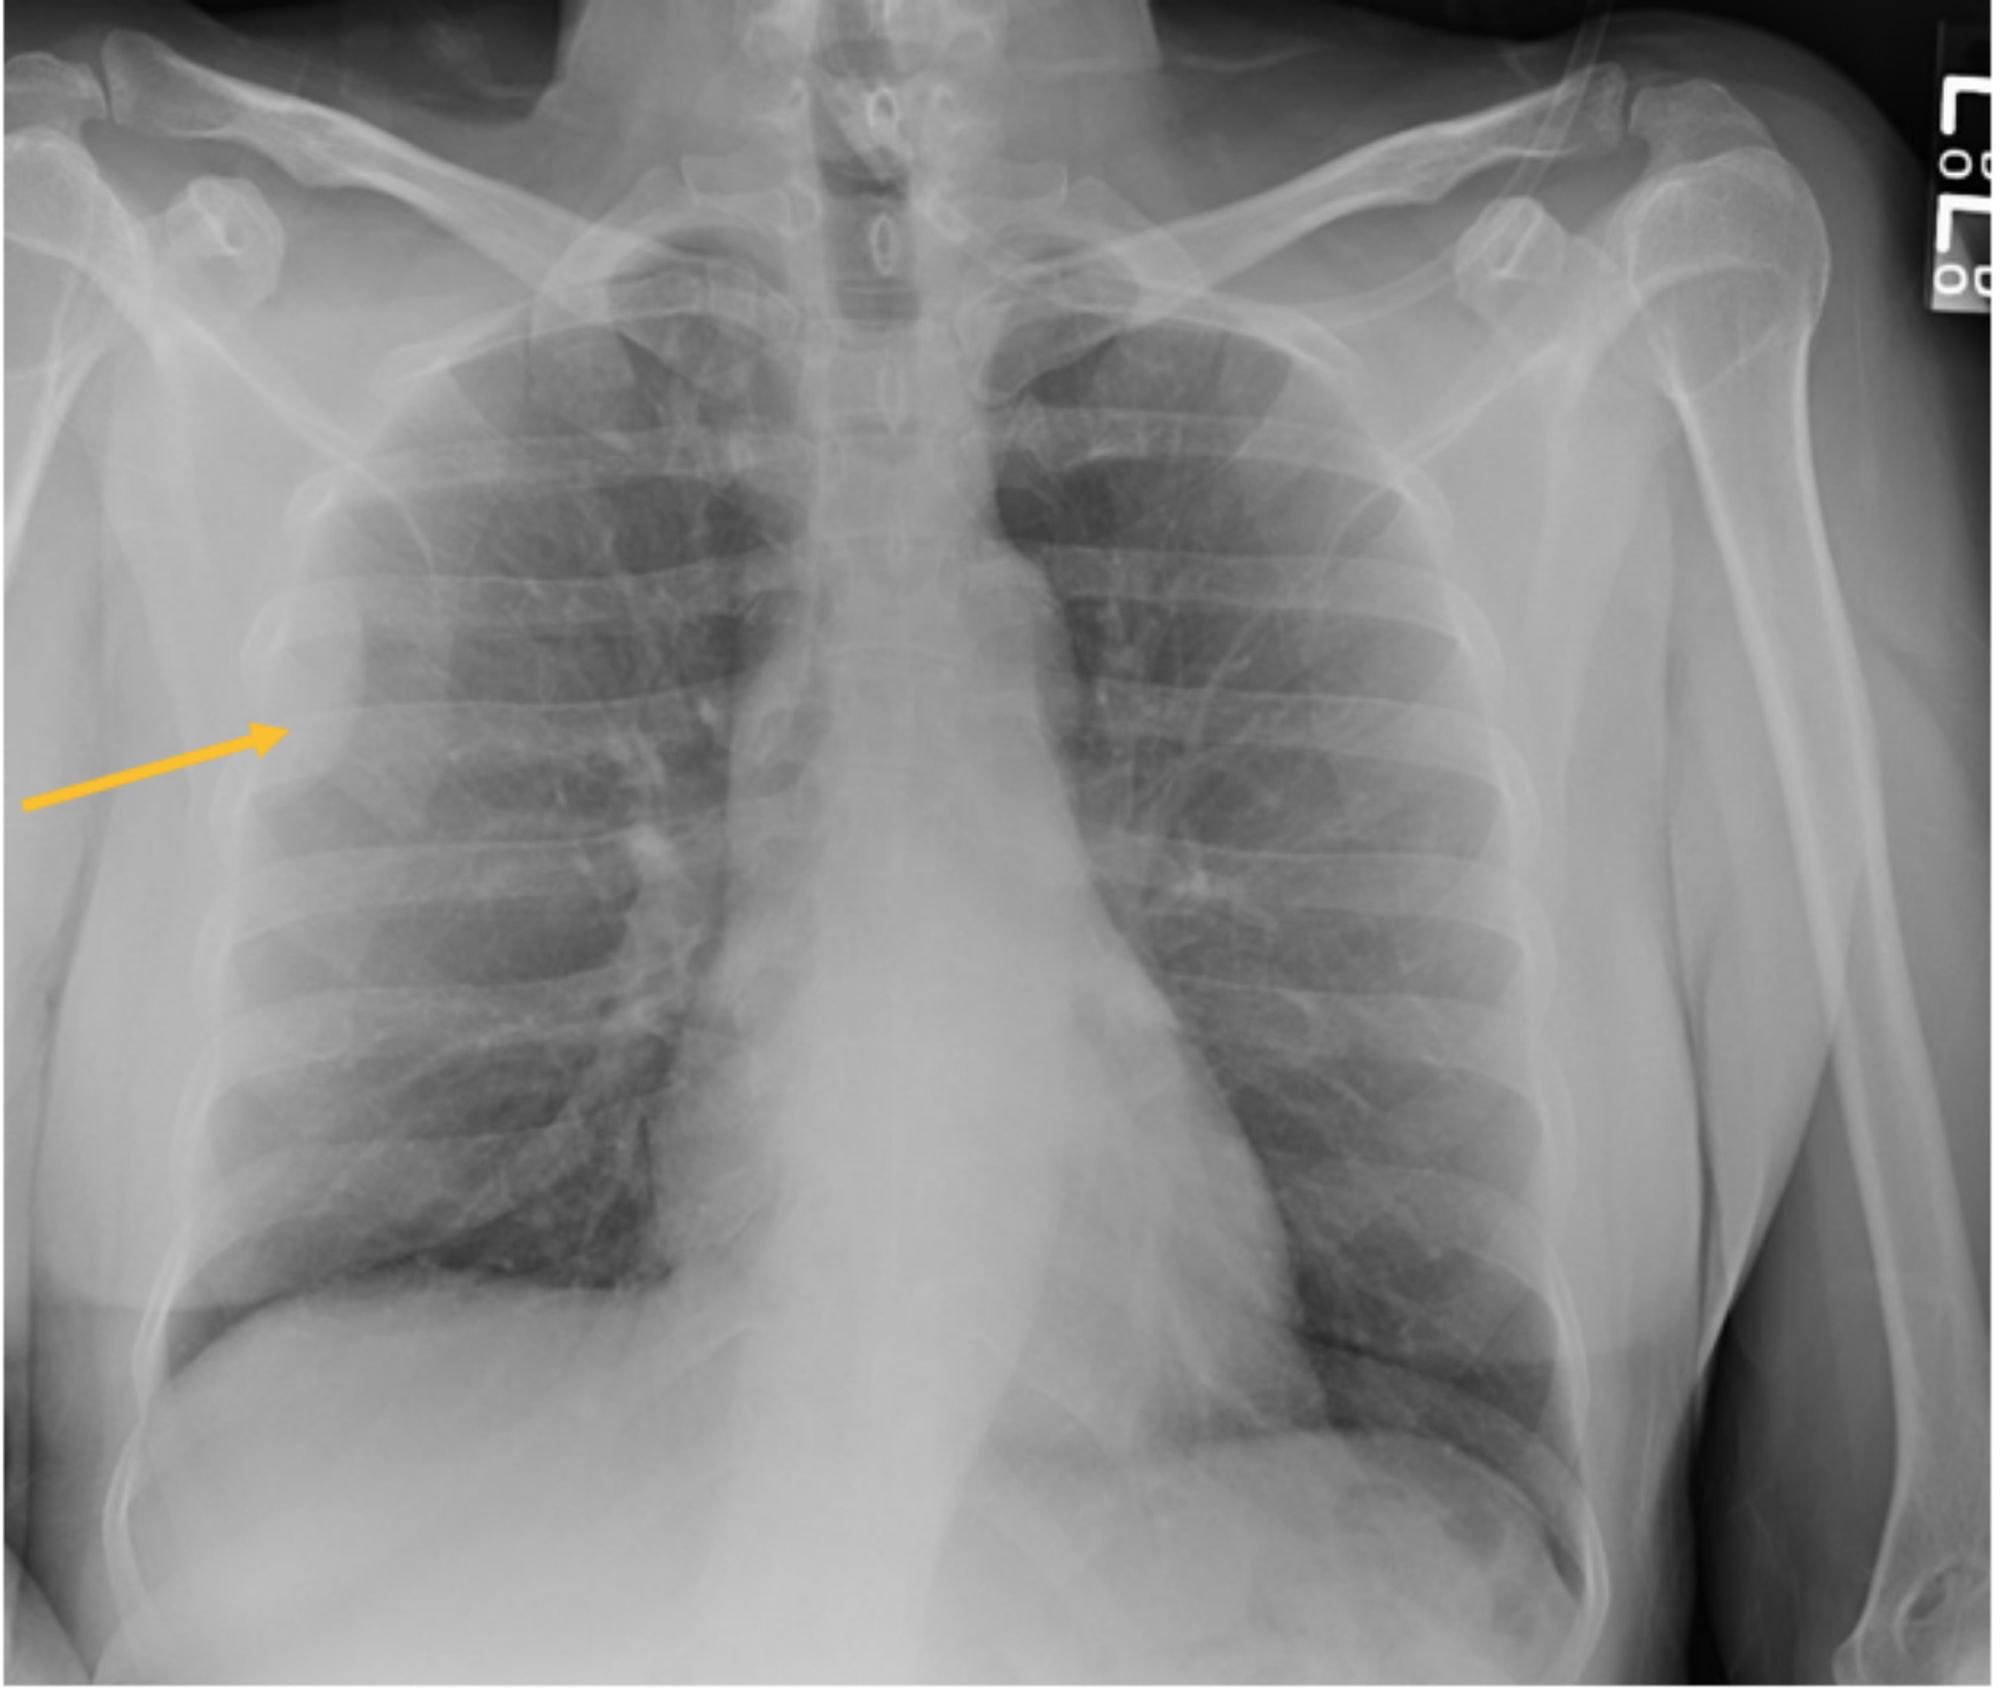

Anterior mediastinal tumor (arrow) diagnosed with preoperative chest Heart Tumor X Ray Primary cardiac tumors are very rare; They can be either benign (noncancerous) or. Clinical features, such as patient age, location, and imaging characteristics of the mass will determine the likely differential diagnosis. Magnetic resonance imaging (mri) has proved to be very useful in the differential diagnosis between masses and neomasses,. Multimodality imaging plays a pivotal role in diagnosis and surgical. Heart Tumor X Ray.

An unusual presentation of a giant pleural tumor ejournal.gr